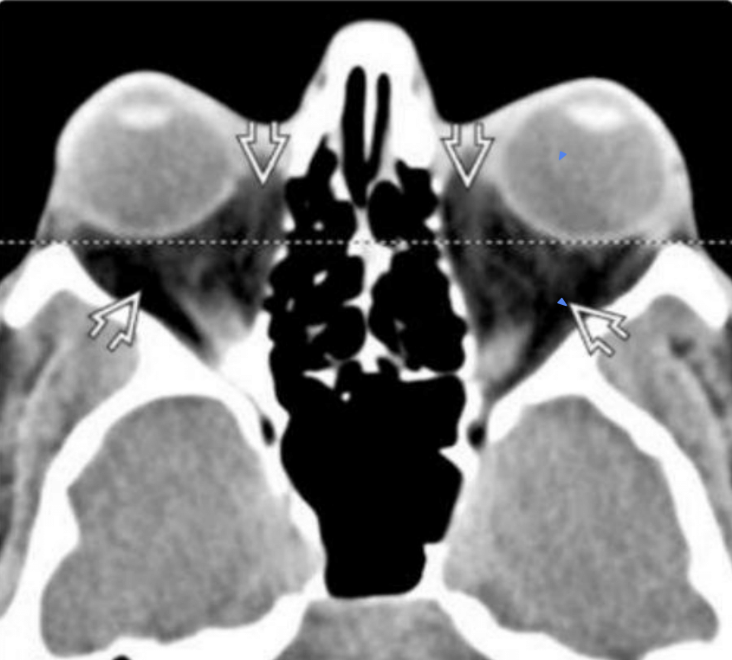

Q

Signo:

¿Qué esperamos encontrar en los métodos de imagen para retinoblastoma?

Calcificaciones “machadas o punteadas” intraoculares

Diagnóstico

Retinoblastoma